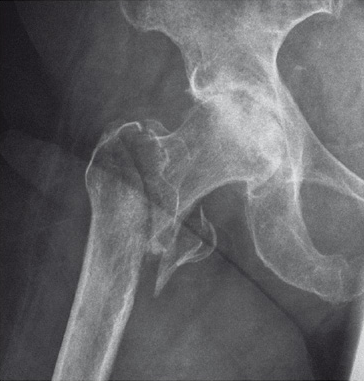

Case 2:

Use of the guide-wire aiming device in an 87-year-old woman.